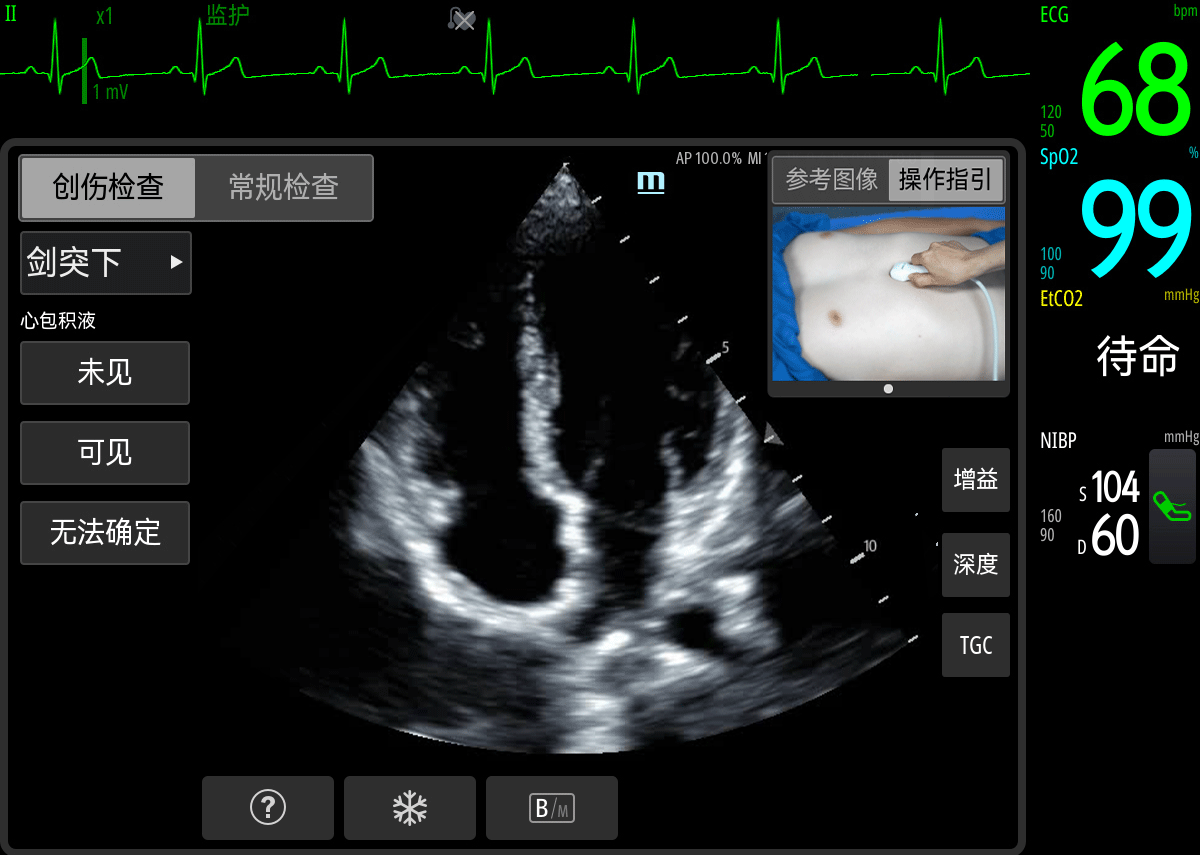

从世界范围内来看,创伤一直是院前急救排名前二的病因,院前应用超声对严重创伤早期识别具有重要的临床价值。

迈瑞的模块化融合超声探头,一扫以往院前超声设备不匹配、使用门槛高两大障碍,提供创伤检查分步指引、打图手法和正常图像参考,帮助非超声专业出身的急救医生更快速完成FAST检查,为后续院内治疗提供依据和参考。